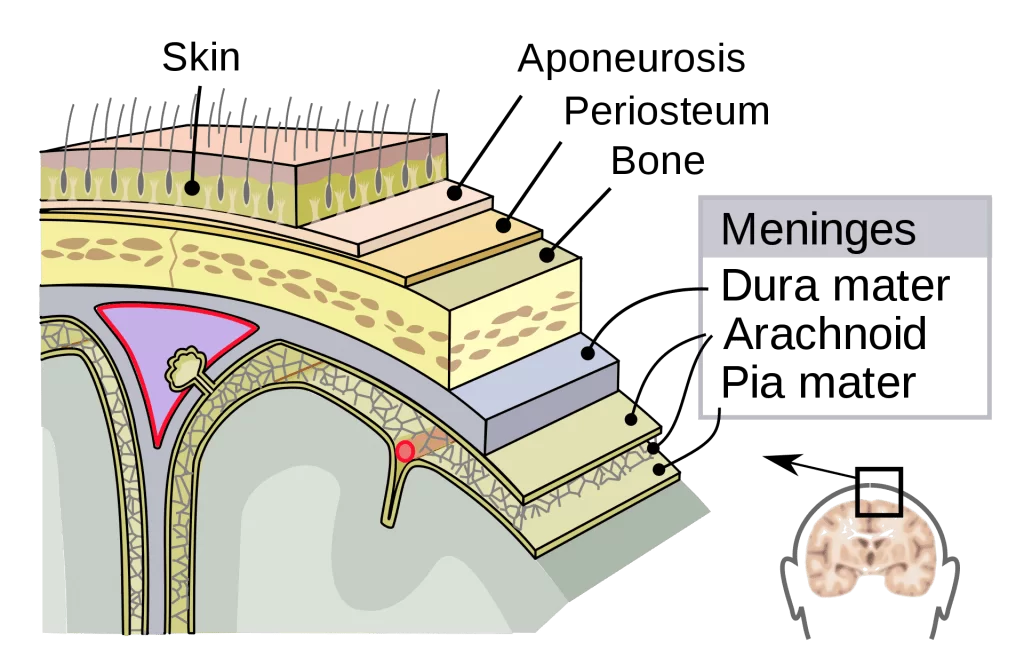

Το υποσκληρίδιο αιμάτωμα είναι συλλογή αίματος κάτω από τη σκληρά μήνιγγα (εξ’ ου και η ονομασία υπο=κάτω, σκληρίδιο=σκληρά μήνιγγα). Για να καταλάβει κανείς που ακριβώς αθροίζεται το αίμα, πρέπει πρώτα να κατανοήσει βασικές ανατομικές έννοιες:

Ανάμεσα στον εγκέφαλο και το κρανίο υπάρχουν 3 περιβλήματα, οι μήνιγγες. Αυτές είναι από έξω προς τα μέσα: η σκληρά, η αραχνοειδής και η χοριοειδής μήνιγγα. Το υποσκληρίδιο αιμάτωμα αθροίζεται (μαζεύεται) ανάμεσα στη σκληρά και την αραχνοειδή μήνιγγα (Εικόνα 1).

Σε αντίθεση, στα επισκληρίδια αιματώματα το αίμα αθροίζεται εκτός της σκληράς μήνιγγας και συγκεκριμένα ανάμεσα στο κρανίο και τη σκληρά μήνιγγα (Εικόνα 2).